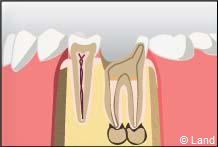

La pulpe est atteinte par la progression de la carie. Il y a donc un risque non négligeable de voir apparaître un foyer infectieux au bout de la racine.

1° Le chirurgien-dentiste va donc procéder à la dévitalisation* de la dent ; en clair il va extirper de la partie centrale de la dent avec les instruments adéquats, soit manuellement soit mécaniquement, la pulpe dentaire constituée de filets nerveux et de très fins vaisseaux sanguins. Cette étape permet d’enlever la totalité des tissus nécrosés ou infectés et de procéder à un nettoyage soigneux anti bactérien.

2° Il doit ensuite mettre en forme le canal afin de pouvoir réaliser l’obturation canalaire, le plus souvent à l’aide de gutta-percha chauffée ou froide permettant d’obtenir une étanchéité de bonne qualité afin de prévenir toute ré-infiltration par des bactéries et d’assurer sur le long terme la conservation d’une dent assainie. S’il y avait une lésion infectieuse au bout de la dent, celle-ci guérira, si elle n’est pas déjà trop avancée.